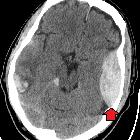

In almost all cases, extradural hematomas are seen on CT scans of the brain. They are typically bi-convex (or lentiform) in shape, and most frequently beneath the squamous part of the temporal bone. EDHs are hyperdense, somewhat heterogeneous, and sharply demarcated. Depending on their size, secondary features of mass effect (e.g. midline shift, subfalcine herniation, uncal herniation) may be present.

When acute bleeding is occurring at the time of CT scanning the non-clotted fresh blood is typically less hyperdense, and a swirl sign may be evident .

Prognosis, even with a relatively large hematoma, is in general quite good, as long as the clot is evacuated promptly. A smaller hematoma without mass effect or swirl sign can be treated conservatively , sometimes resulting in calcification of the dura.